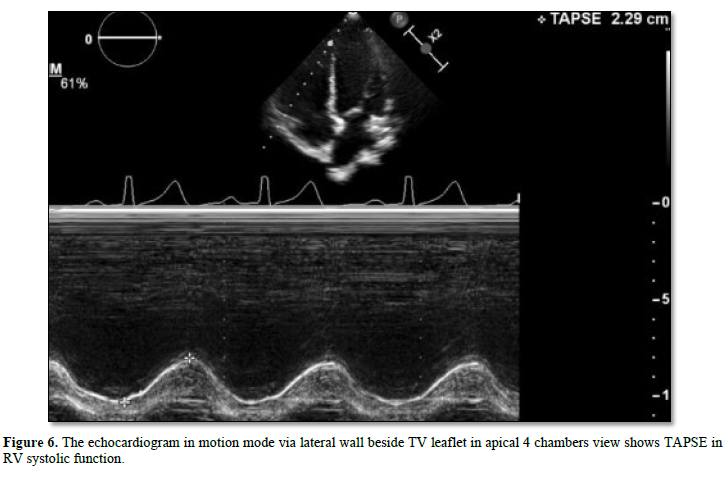

The reason for coronary artery relocalization procedure has influence to the coronary supply and regional wall motion of LV Although the main of pumping was the left sided ventricle (after repair). But in several cases the morphology of main ventricle was more trabeculation or noncompacted. This point was considered evidence of reducing ventricular pumping and related to impair ventricular function. The left ventricular ejection fraction (normal LVEF > 55%) in systolic function, the circumferential or longitudinal strain was important parameter for described neo-left ventricular function [10]. (Normal global longitudinal strain -15% to -22%) [19]. After some report use -20% cut off point for considering normal [20]. However, the right ventricular function was also necessary, in addition the tricuspid annulus plane exertion which is a parameter for evaluating RV function and many cut points in several main diseases such as in pulmonary hypertension if TAPSE < 1.6 cm. (since 1.5 cm. below) It’s being able to detect elevated pulmonary pressure in patients with interstitial lung disease who underwent cardiac catheterization [21]. (Accept rang > 1.5 cm.) There is also tissue Doppler velocity of S' wave at lateral wall beside leaflet of the tricuspid valve that can be a parameter used to evaluate RV function. (Normal > 11.5 cm/s) [22]. About the diastolic function E/E’ at mitral valve inflow able to reflect the filling pressure of LV and LA contraction. The peak velocity of E wave of mitral valve inflow by pulse wave Doppler (Figures 5-8) and the peak velocity of E’ wave of tissue pulse wave Doppler able to ratio E/E’ if greater than 15 may be related to elevate left atrial pressure, such as mitral stenosis or regurgitation and pulmonary vein stenosis or pulmonary hypertension. (Normal < 15) [23].